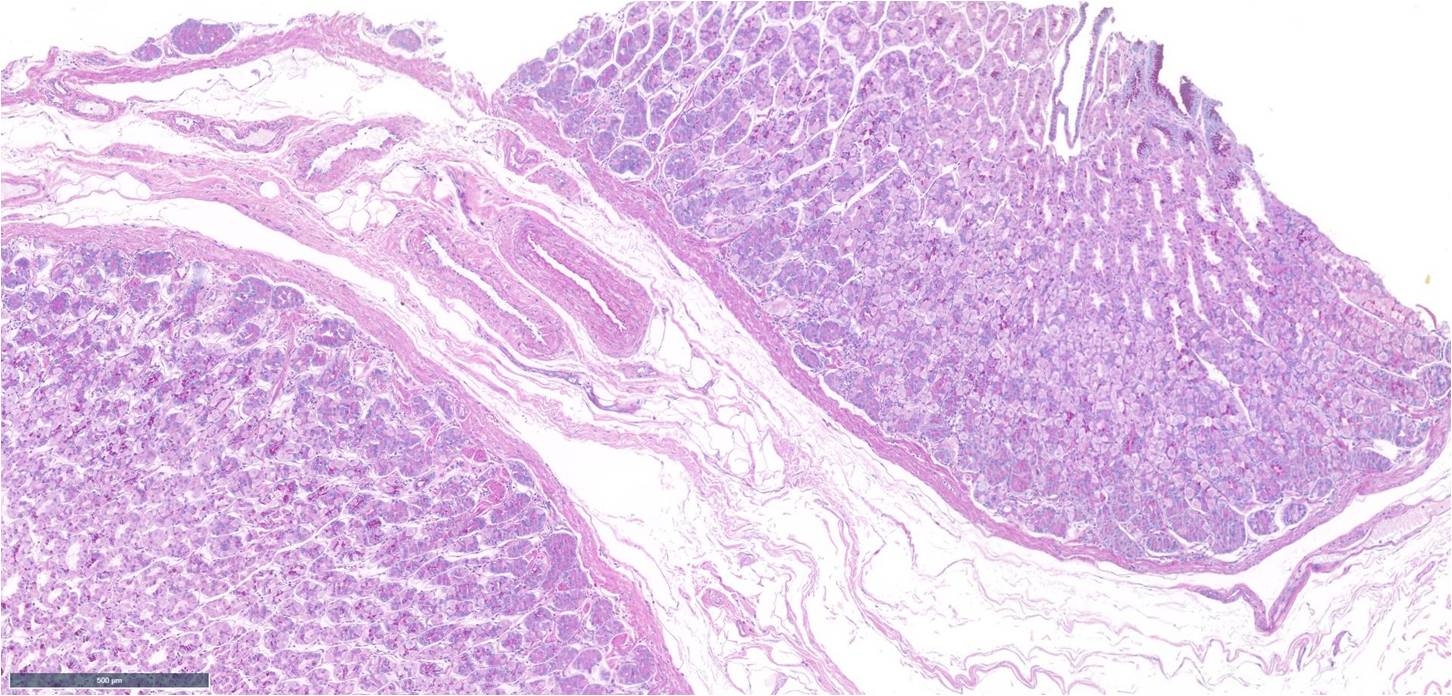

Abdomen 5mm punch biopsy. Active lesion ? papular urticaria